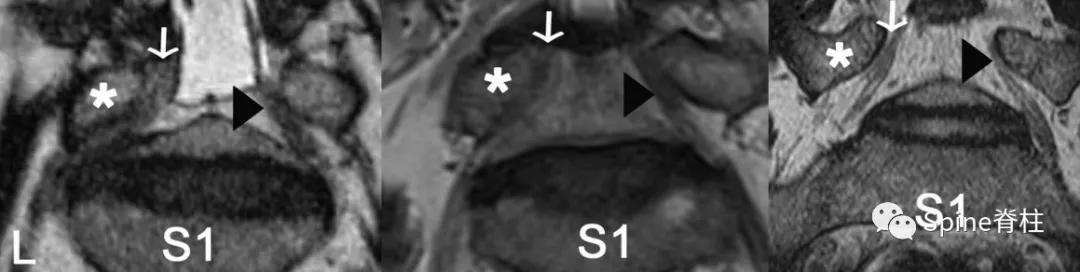

图示:L5脊神经的椎间孔角(FSN),如大于10度,则症状性可能性大。L5脊神经与L5下终板之间形成α和β角,正常椎间孔角应介于α和β角之间

图示:斜冠状位磁共振成像,以L5脊神经为代表。L5脊神经在L5椎弓根(*)和L5-S1椎间盘之间通过。

- 左侧图: 在腰椎间孔外狭窄组中,左侧L5神经是引起症状的(白色箭头),而右侧无症状(黑色箭头)。

- 中间图: 在L4-5椎管内狭窄组中,左侧L5神经为症状性侧(白色箭头),右侧为无症状性侧(黑色箭头)。

- 右侧图: 在正常人组中,显示的右侧(白箭头)和左侧(黑箭头)L5脊神经。